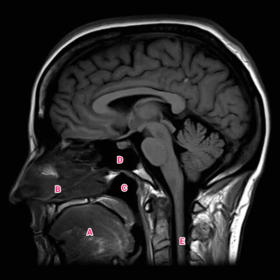

Anatomy practical midyear flashcard revision

anatomy

x-ray